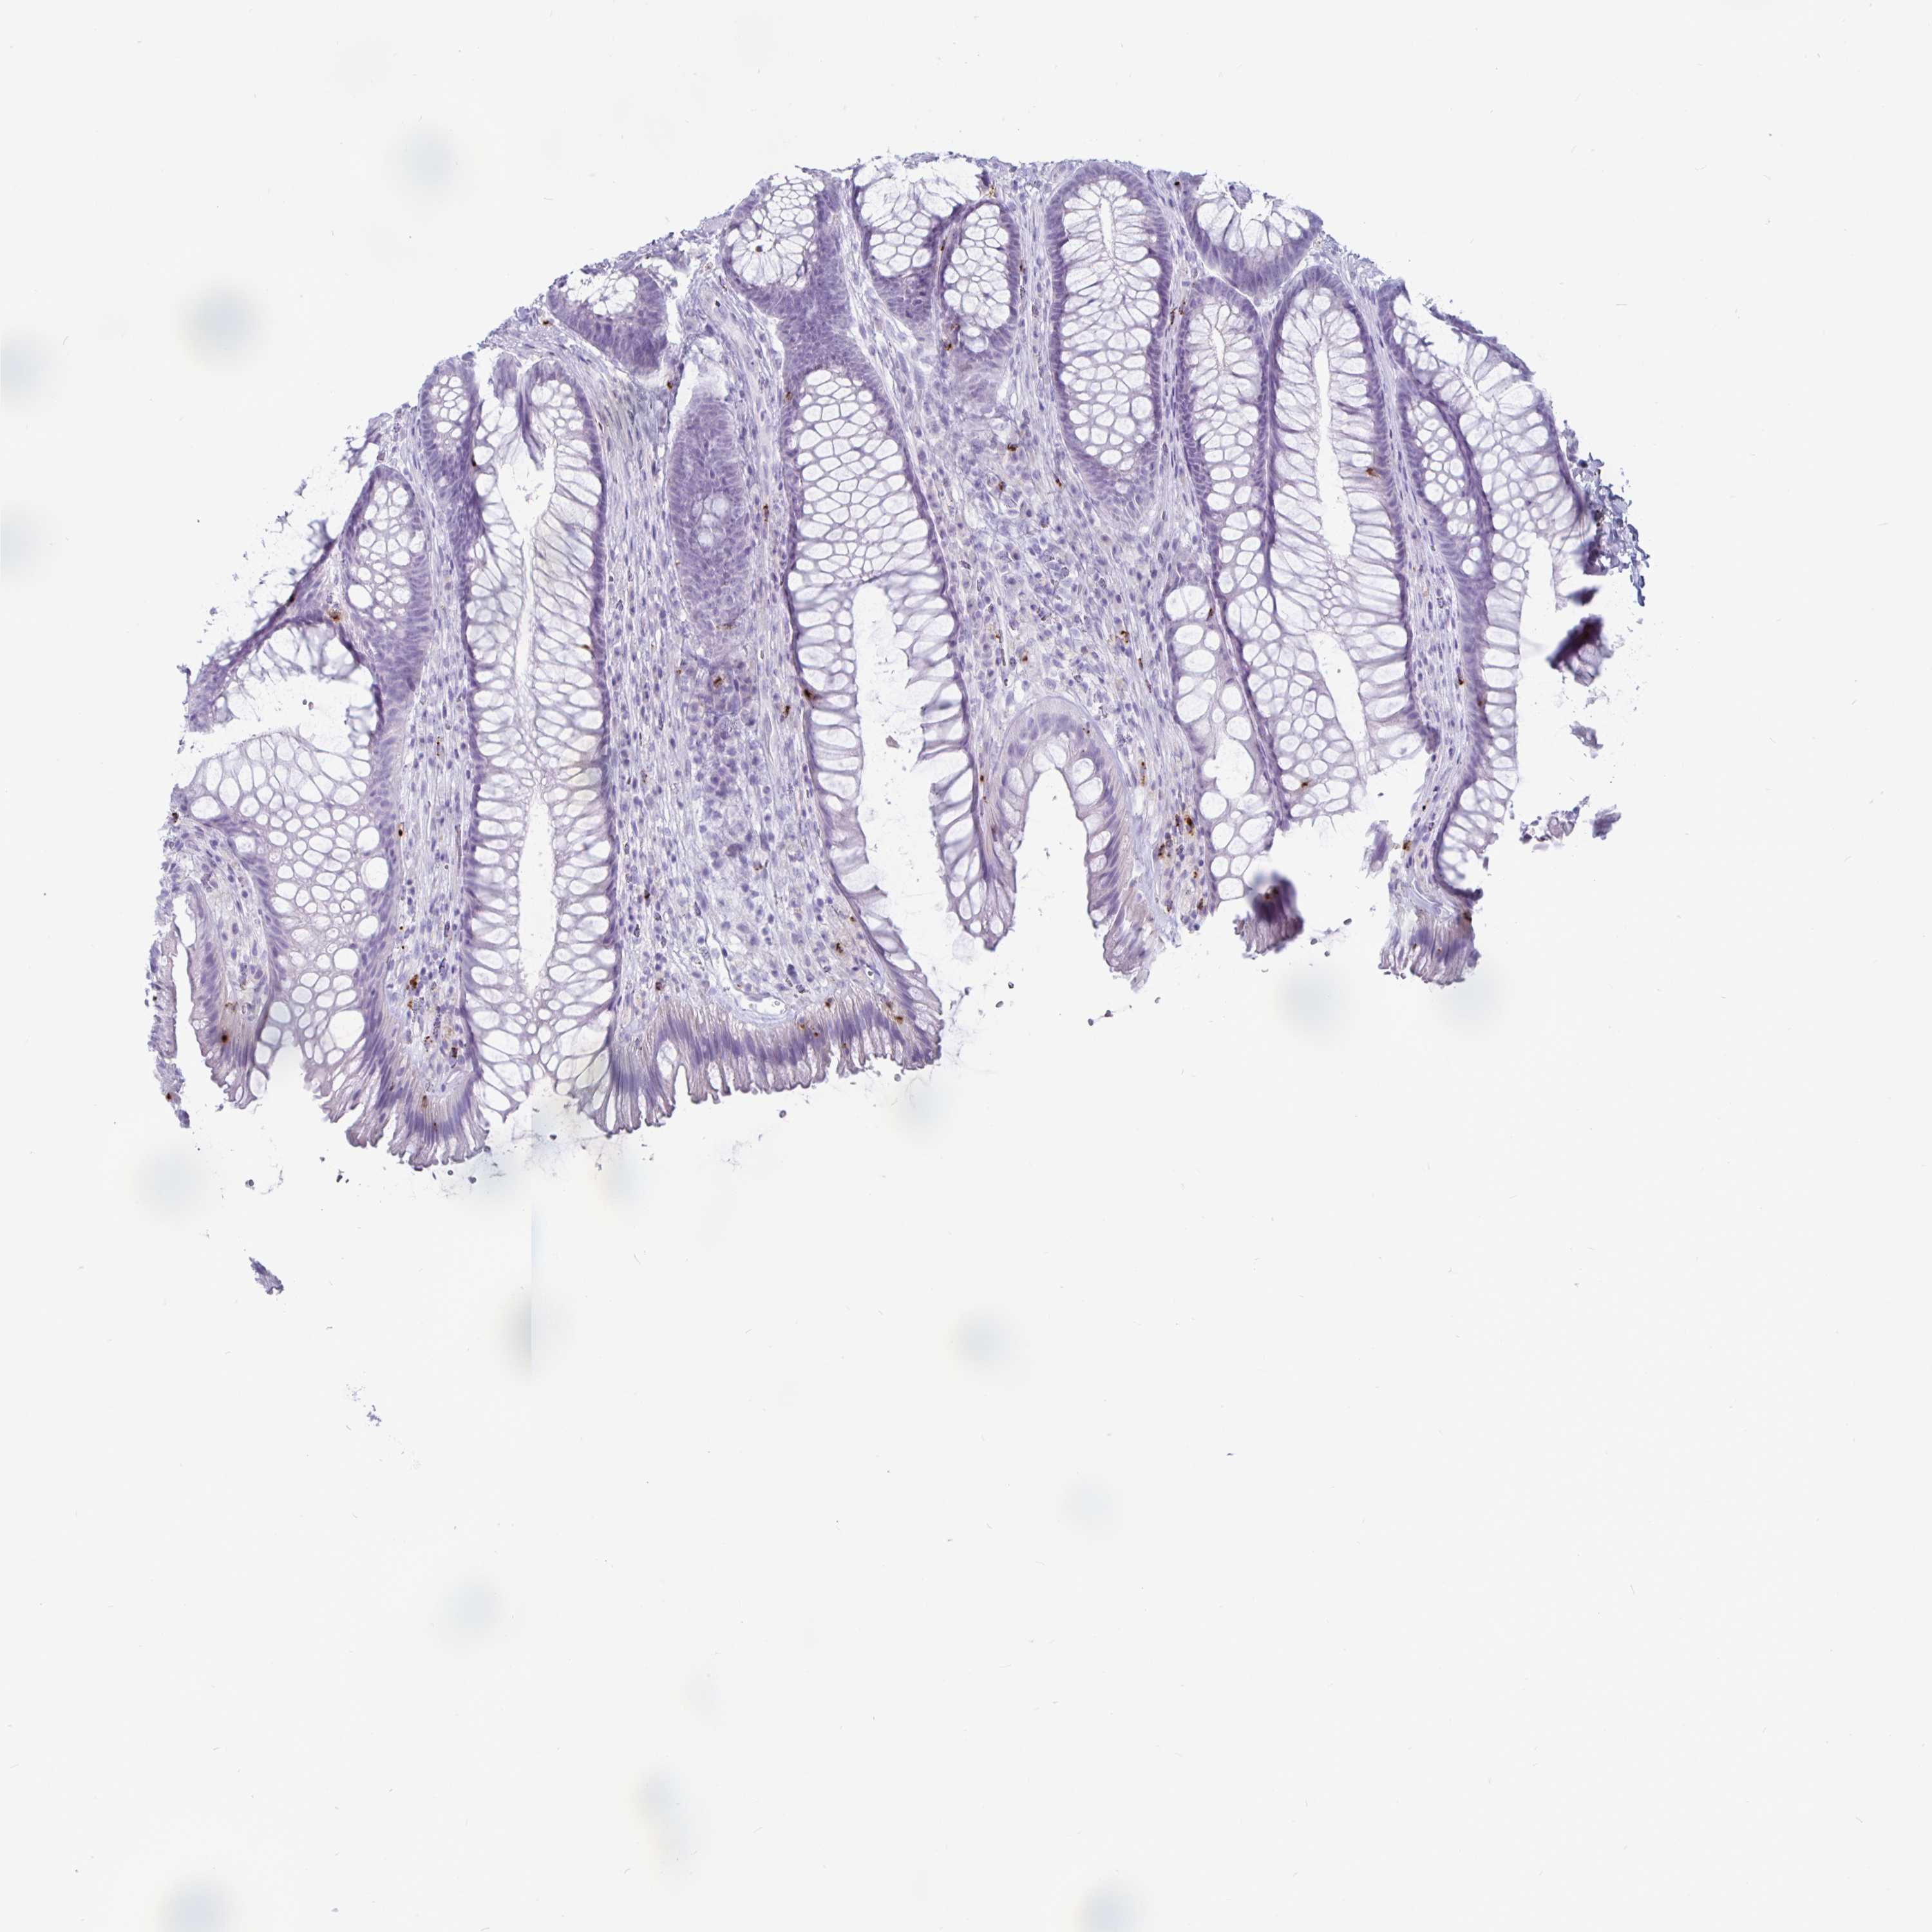

TISSUE PRIMARY DATA RECTUM Show tissue menu

RECTUM - Antibody stainingi

Antibody staining in the annotated cell types in the current human tissue is reported as not detected, low, medium, or high, based on conventional immunohistochemistry profiling in selected tissues. This score is based on the combination of the staining intensity and fraction of stained cells.

Each image is clickable and will lead to virtual microscopy that enables deeper exploration of all samples and also displays staining intensity scores, fraction scores and subcellular localization as well as patient and tissue information for each sample.

Antibody HPA063181Antibody HPA065895

Glandular cells Not detectedNot detected